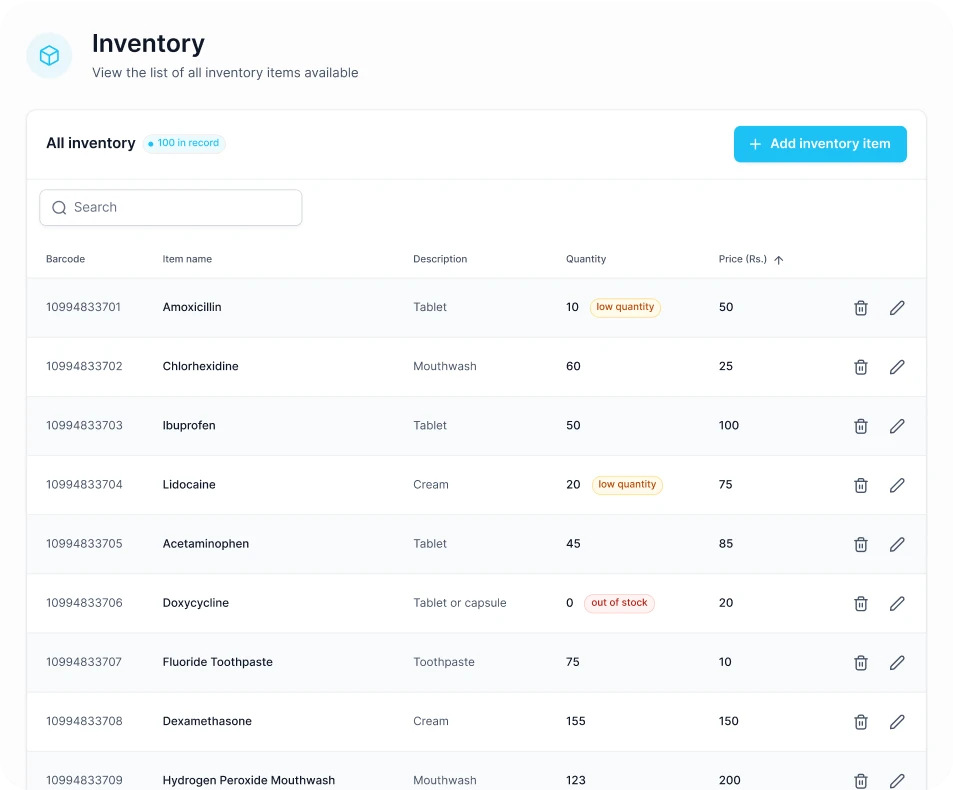

DoxOptima streamlines clinic operations with automated workflows, intuitive tools, and real-time insights, simplifying appointments, patient records, staff management, and finances for enhanced efficiency